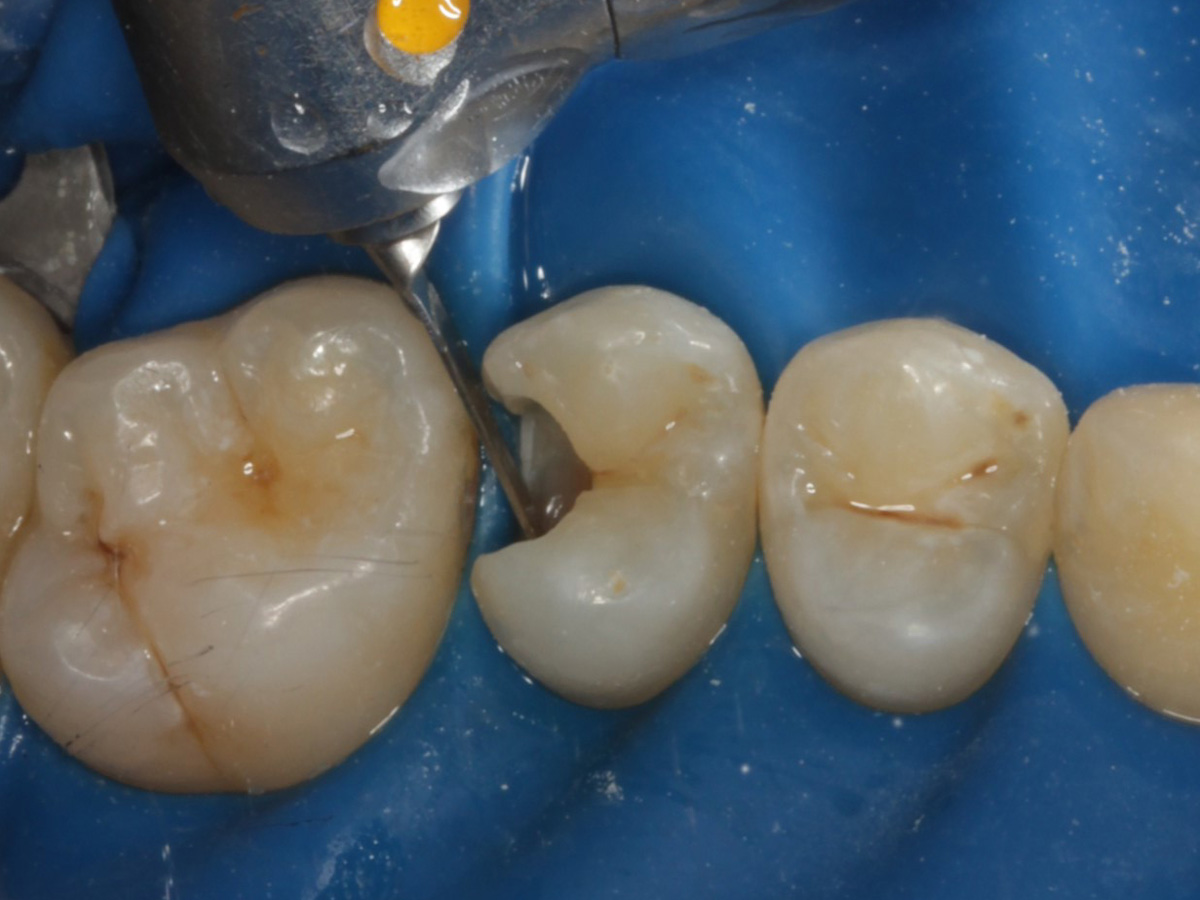

Abbildung 16

Überschussentfernung/ „Anpolieren“ u.a. trocken mit Sandpapierscheibe

Abbildung 17

Zahnseidenkontrolle: kein Überschuss, satter Kontaktpunkt

Abbildung 18

Fertige Restauration